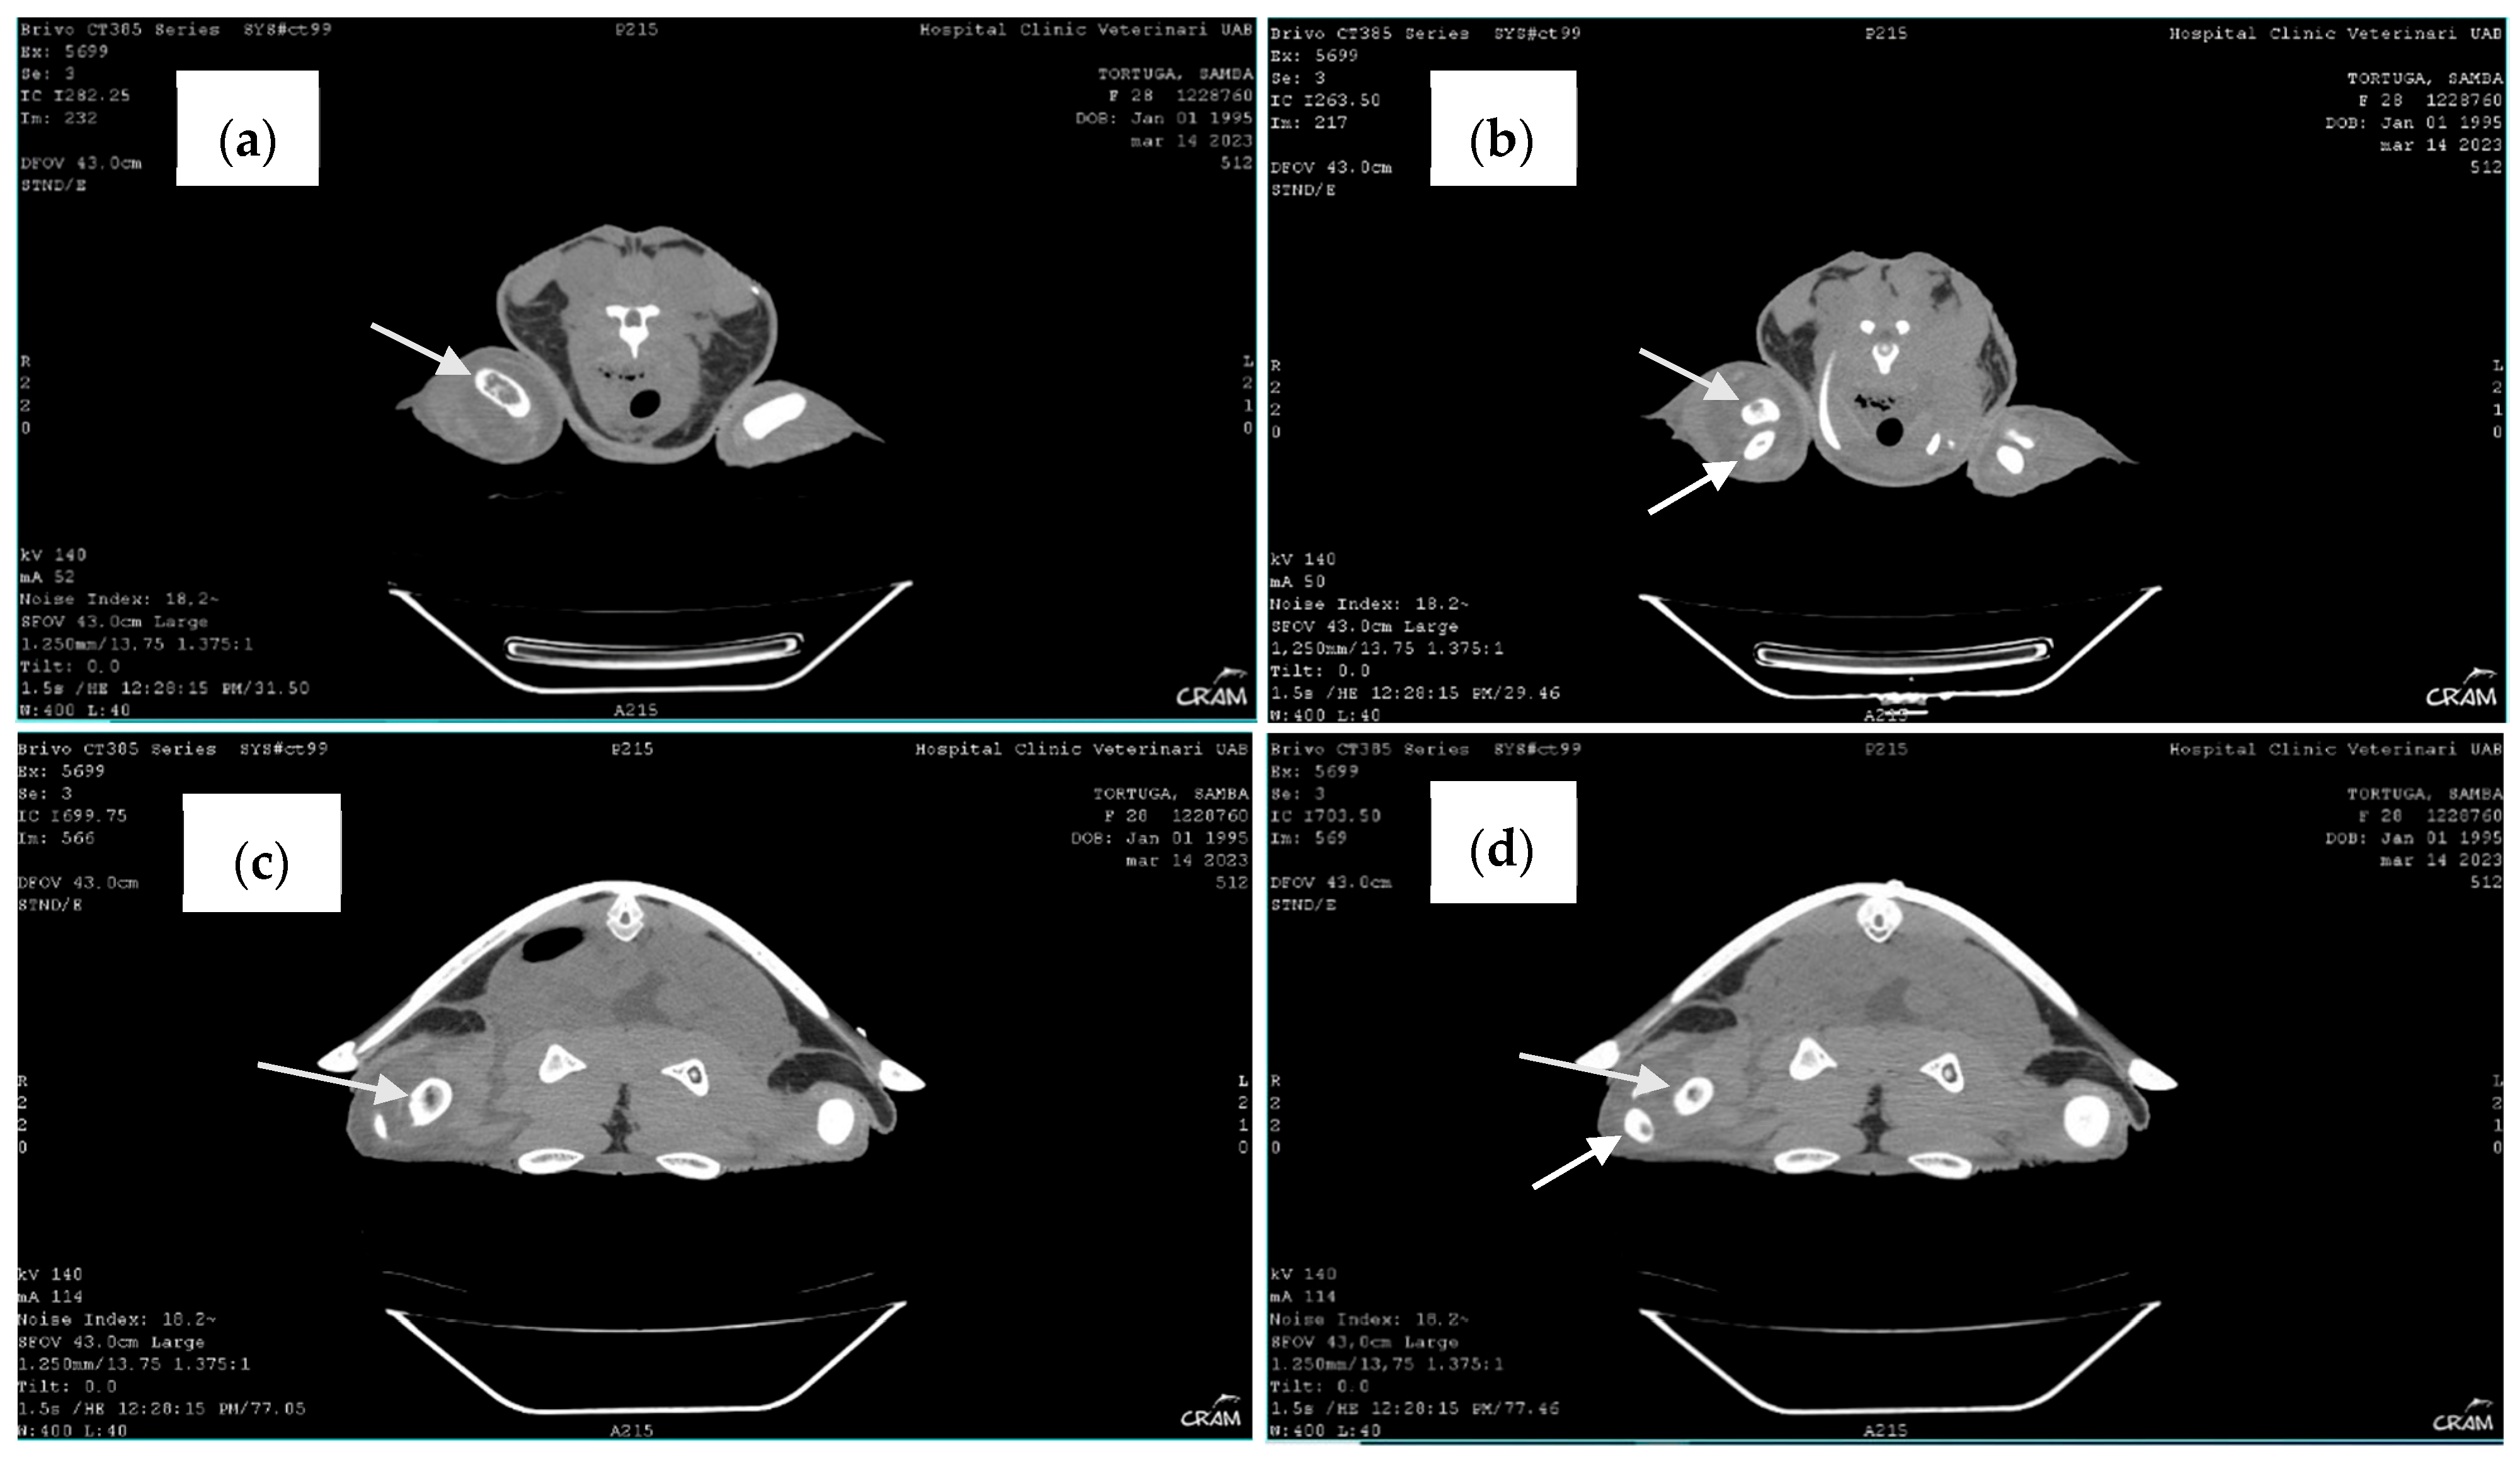

Therefore, to better visualize the lesions, computed tomography (CT) of the whole body, in soft tissue and bone algorithm, with 1.25 mm thick sections, without administration of intravenous iodinated contrast, was performed. CT confirmed the lytic lesions observed in radiography on the distal right humerus, proximal right radius and ulna, distal right femur, and proximal right tibia and fibula. When clinical signs appeared, blood culture at 24–26 °C with antibiogram was performed, revealing a positive result.

Late-stage lesions after five months of rehabilitation were characterized by sclerosis and remodeling of the lesion borders (Figure 7). Lesions occurring within the bone shaft typically remain asymptomatic. However, those adjacent to the joint surface, known as juxta-articular lesions, may advance to structural deterioration of the joint surface, leading to symptoms such as pain and restricted movement. CT revealed additional lytic bone lesions of the left ischium, ileum, and pubis; right ischium; left humerus head; and confirmed the lytic lesions observed via radiography (Figure 8). Throughout the treatment period, the animal continued to have a healthy appetite and was bright and alert according to Manire et al. 2017, Sea Turtle Health & Rehabilitation [22]. Blood samples were taken once a month to evaluate hematological and biochemical values, and all the parameters were in range according to plasma biochemical and hematological baseline values in loggerhead sea turtles from the Mediterranean Sea proposed by Basile et al. (2011) [19].

Figure 8.

Computed tomography. Note bone lysis on the distal end of the right humerus (arrow) (a), the proximal end of the right radius and ulna (arrows) (b), and the proximal end of the right tibia and fibula (arrows) (c,d).

X-ray is the initial imaging of choice for diagnosis and evaluation of bone lesions. Although radiography showed decalcification and cystic lesions on some bones, it demonstrated a lower sensitivity compared to the CT. One of the hypotheses is that the lesions observed in March 2023 were caused by the decompression sickness event that occurred four years earlier, representing a case of DON. DON is rare but remains extremely important to be recognized as a potential complication of DCS [5,6,11].

Additional imaging techniques such as CT scans should be used for early diagnosis of dysbaric osteonecrosis when an X-ray does not reveal any lesions, especially for those animals who have a history of decompression sickness and/or joint symptoms. Clinicians should be aware of the possibility of osteolytic lesions for hypothermia, osteomyelitis, and DON in rehabilitation of sea turtles and should pursue additional diagnostic testing [24]. Given the high frequency of sea turtles diagnosed with gas embolism after bycatch over recent years, DON should be considered in differential diagnosis of osteolytic lesions in marine turtles.